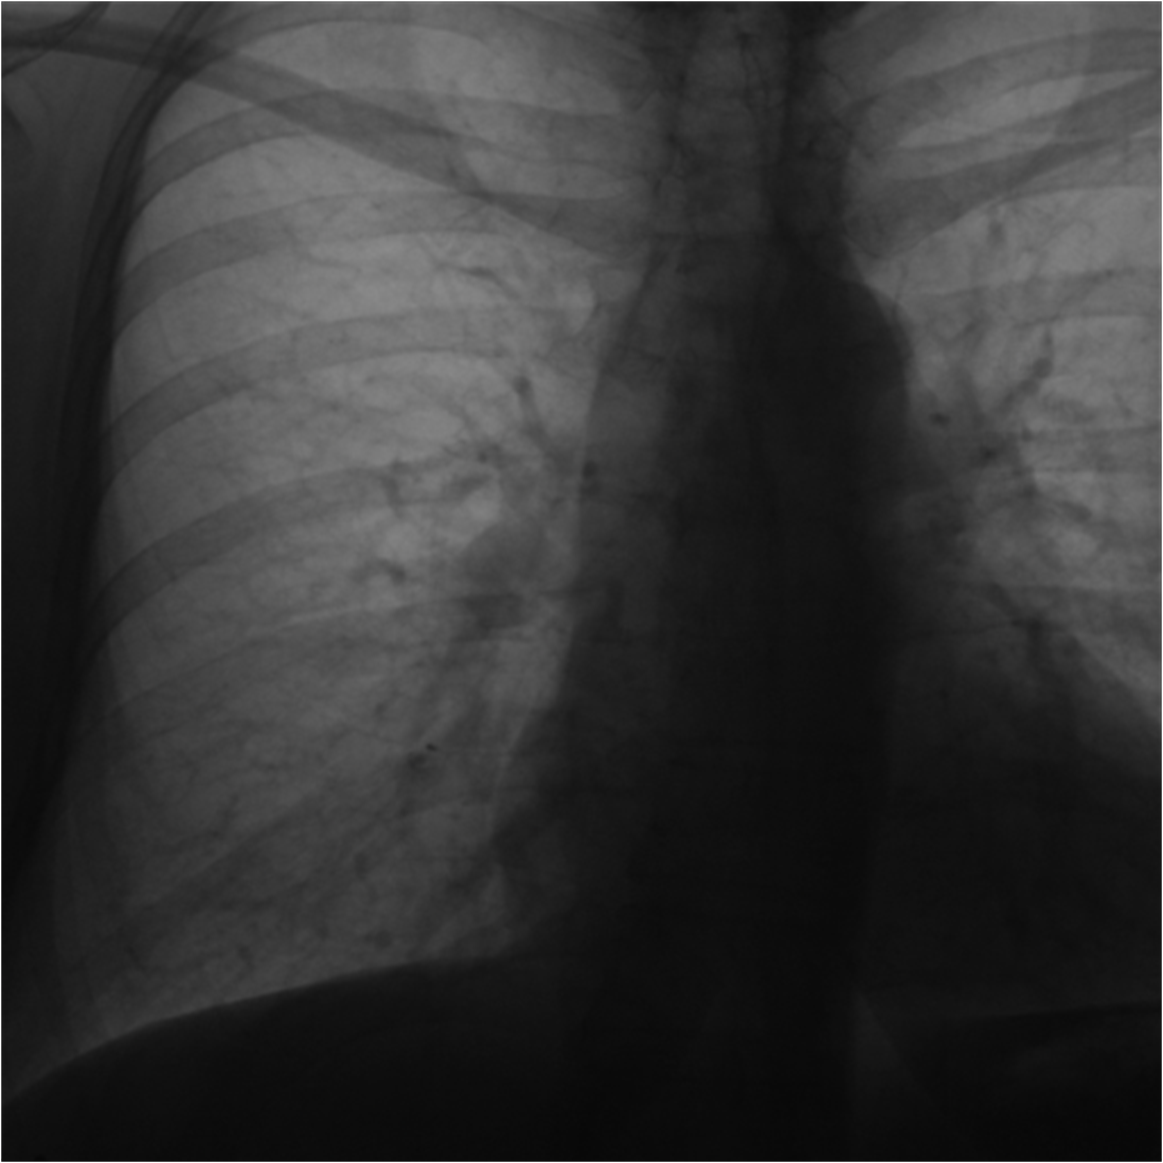

2.2.1 Fluoroscopy Decomposition

We used a Deep Adversarial Decomposition approach[13, 21] to eliminate image artifacts caused by the FG and radiopaque fiducials. The input to our network was the patient fluoroscopic image with the FG mounting frame, as shown in Fig. 2A. The two outputs comprised the residual image containing the extracted artifacts (Fig. 2B) and the artifact-free patient fluoroscopic image (Fig. 2C). Fiducials (dark dots induced by the aluminum spheres) were easily identified in the residual image due to their high contrast appearance. As the details of this fluoroscopy decomposition technique were discussed in our previous work [13], this paper focuses on the navigation problem.